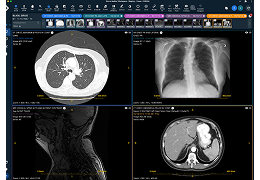

人工智能不再是一项抽象的承诺。Eclipse 引擎为 ImageView 软件提供支持,将 AI 付诸于无可争议的行动,即通过成像智能、工作流智能和分析智能推动产生具体、可衡量的结果。

成像智能。

Eclipse 成像智能功能提供强大的处理能力和最佳质量的影像,同时减少质量错误并提高剂量效率。

凭借 AI、专有算法和先进的影像处理能力,提供出色的影像质量和无与伦比的诊断信心。